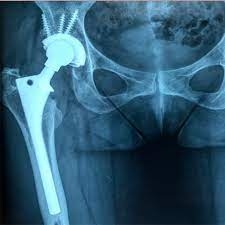

Como se preparar para uma cirurgia do quadril?

Preparar-se para uma cirurgia do quadril é um passo muito importante para os resultados pós-operatórios e a recuperação do paciente. Aqui estão algumas orientações abrangentes para ajudar indivíduos a se prepararem de maneira eficaz para esse procedimento.